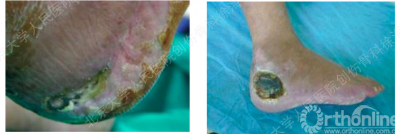

困惑之处

你会像下图所示,选择外侧扩大入路的方式操作吗?

一般的共识是通过外科手术是治疗跟骨关节内骨折的有效方法, “L”形外侧扩大切口是最常用的经典入路。因为这种入路方式能够提供损伤的全面暴露并避免对腓骨肌腱和腓肠神经的损伤。然而,这种入路方式也存在着明显的劣势:

伤口愈合慢

易发生皮瓣坏死或感染皮

软组织并发症率高

距下关节僵硬、活动丧失

一般需要两周左右时间才能手术